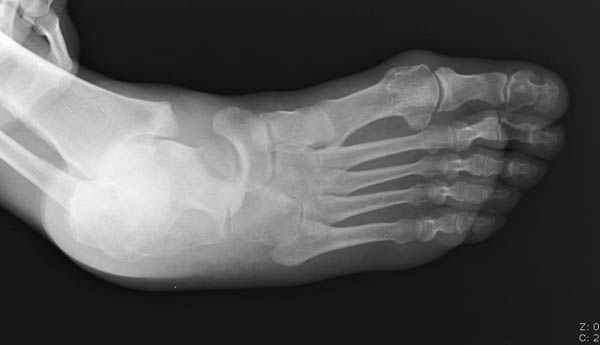

Уважаемые участники русского Ортофорума, поздравляю всех со всеми прошедшими праздниками: Новым годом, Рождеством, Hanukkah, Kwanzaa, желаю участникам всего наилучшего и здоровья.Повреждение таранной кости.Больной 81г автоавария, повреждение таранной кости, здесь снимки. Какие рекомендации?Djoldas Kuldjanov, MDDepartment of Orthopedic SurgerySt. Louis University Medical Center

Вдогонку по поводу перелома таранной кости, больная 81, не страдает диабетом, перелом закрытый, в первый же день поступления ограничились временным наружным фиксатором (как на снимке).

За пару недель насчитал 5 больных с переломом таранной кости, из них двое с двусторонним повреждением.

Из-за отека на стопе тактика лечения у всех была

одинаковая: временная наружная фиксация до спадения отека, при изолированных переломах они выписывались домой и через дней 7 госпитализировались на оперативное лечение.

Примеры на снимке...